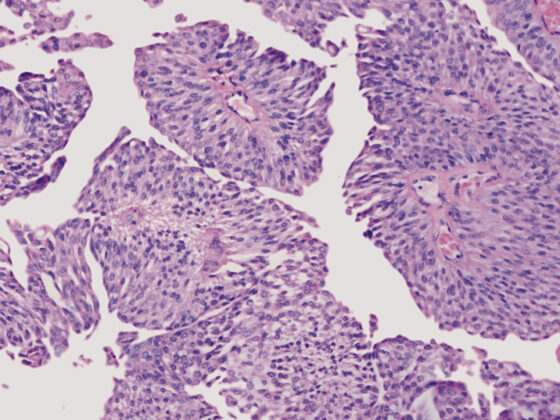

Im Modul über das nicht-kleinzellige Lungenkarzinom (NSCLC) des Swiss Oncology in Motion moderiert Prof. em. Dr. med. Richard Herrmann Vorträge von Prof. Dr. med. Solange Peters (Département d’oncologie, Université de Lausanne & Centre hospitalier universitaire vaudois), Dr. med. David König (Klinik für Onkologie, Universitätsspital Basel) und Prof. Dr. Dr. Sacha Rothschild (Onkologie & Hämatologie, Kantonsspital Baden). In diesem Modul erlangen Sie einen Überblick zu verschiedenen Tumorstadien des NSCLC und der Behandlungsmöglichkeiten bei resektablen und nicht-resektablen Stadien. Zudem erhalten Sie Informationen zu wichtigen Studienergebnissen und den verfügbaren zielgerichteten Therapien.